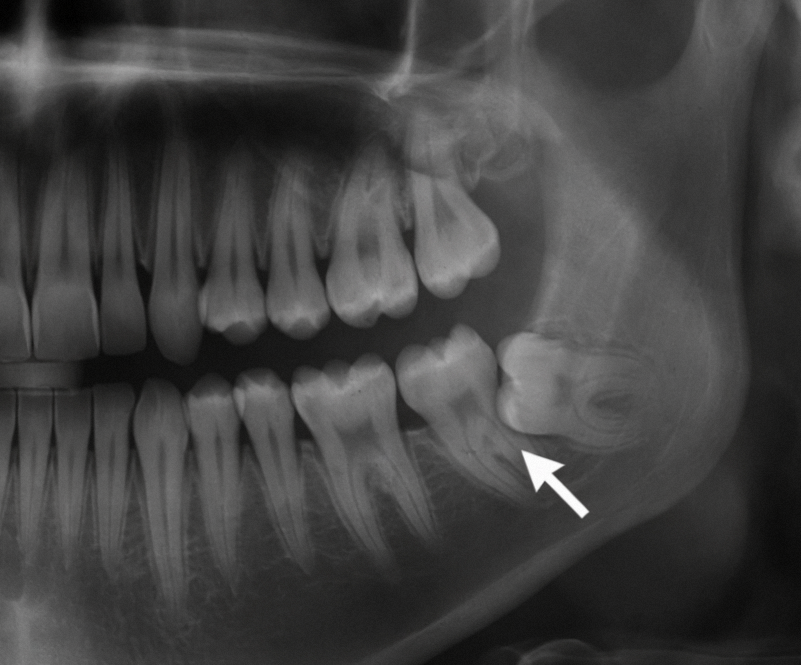

- CT 촬영의 중요성

많은 분께서 엑스레이 한 장을 찍고

발치 여부를 판단한다고 생각하십니다.

그러나 파노라마는 2차원 영상입니다.

즉, 치아의 뿌리와 주요 구조물과의

실제 거리, 위치 관계, 접촉 여부를

정확히 파악하는 데에는 한계가 있습니다.

만일 신경과 가깝다고 의심되는 경우에는

CT 촬영을 통한 분석이 필요합니다.

이를 통해 치근의 정확한 형태와 방향

신경관의 거리 및 접촉 여부,

주변 뼈의 두께와 구조물의 위치 등

이 정보들을 충분하게 확보되었을 때

발치 계획을 정밀하게 수립할 수 있으며,

예상치 못한 상황을 최소화할 수 있습니다.